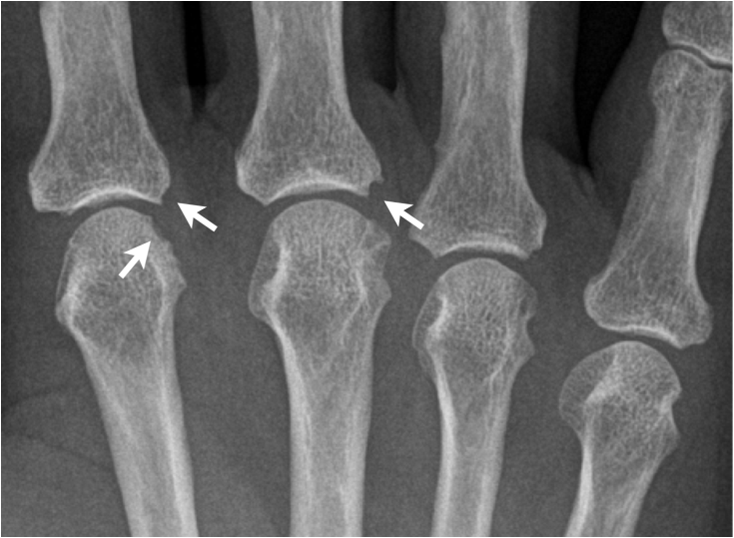

In the hand there is typically involvement of the trapezium-scaphoidal joint and the first carpal-metacarpal joint. In addition, there is involvement of the distal interphalangeal joints of the fingers with lesser changes at the proximal interphalangeal joints and the metacarpal-phalangeal joints.

Fig. 14. Typical degenerative changes in the hand: A) Joint space narrowing and subchondral sclerosis of the trapezoidum-scaphoidal joint and the first carpal-metacarpal joint. B.) Degenerative arthritis of the distal interphalangeal joint showing typical osteophyte formation, joint space narrowing and increased sclerosis.

In the foot there is often involvement of the first metatarsal-phalangeal joint. In addition to joint space narrowing and subchondral sclerosis there is subchondral degenerative cyst formation and osteophyte formation along joint margins. Osteophytes are the sine qua non of osteoarthritis. In degenerative joint disease new bone formation is seen as a response or repair reaction. In inflammatory arthritis there usually is a destruction of bone and osteophytes are not seen.